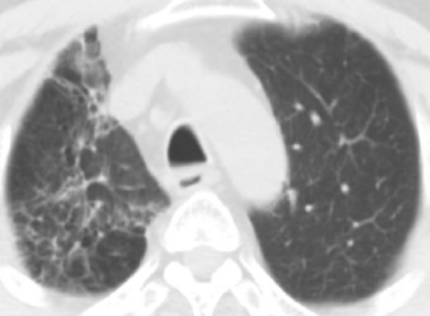

Bgr41Qgrm9eecp6p.jpg yBsczorQ4sRNn4Qo.jpg

放射野内条索影